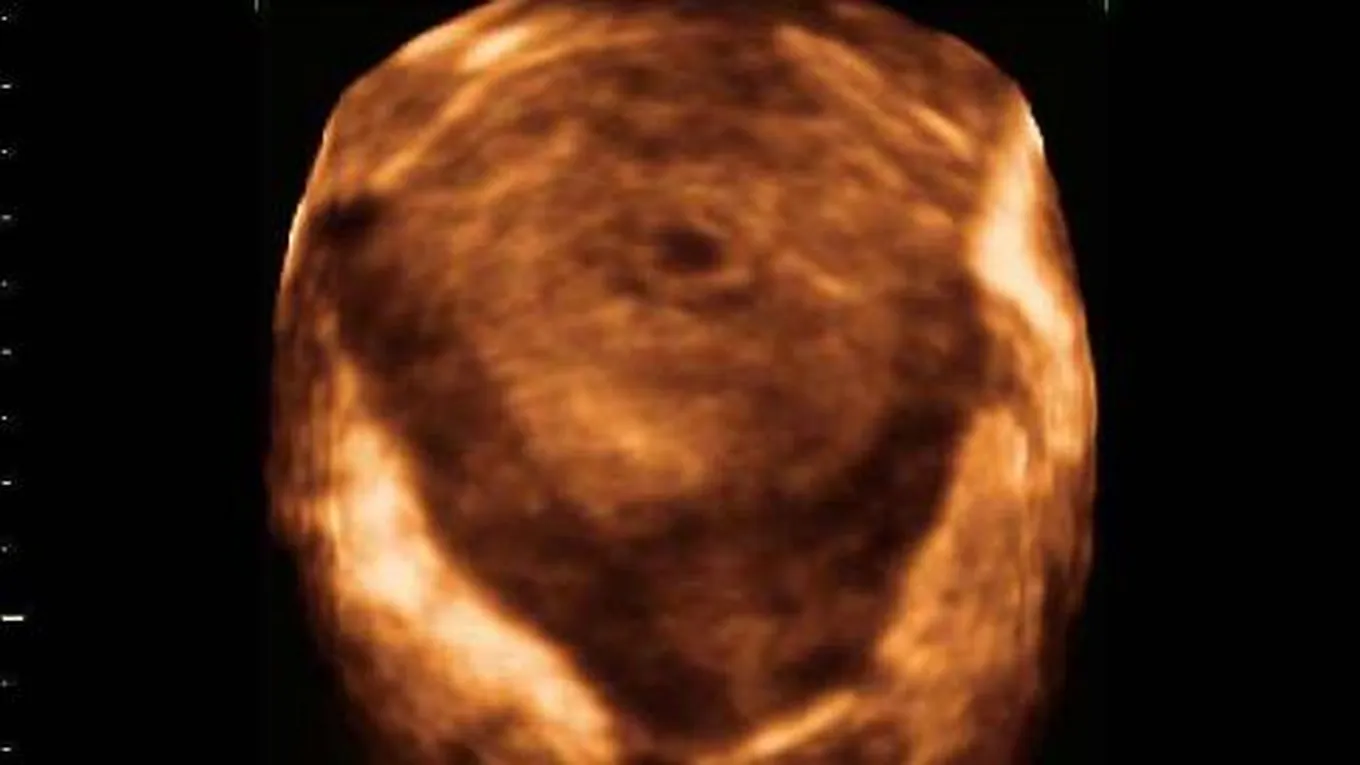

قد لا تشعر الحامل في شهرها الثاني بأيّ اختلافٍ يُذكر عن حملها في الشهر الأول، فلا يزداد حجم البطن ولا تتغيّر علامات الحمل كثيراً عما كانت عليه، وبرغم ذلك فإنّ الشهر الثاني يُعتبر الأهمّ في تشكّل أعضاء الجنين من بين أشهر الحمل الأخرى، لذلك فإنّ أيّ تعرضٍ لعوامل كيماوية وفيزيائية أو تعاطي أدويةٍ غير موصى بها من قبل الطبيب، قد يُشكّل خطراً على الجنين مسبباً له التشوهات الخلقية، وسنذكر في هذا المقال كيف يكون نمو وتطور شكل الجنين في شهره الثاني.

شكل الجنين في الشهر الثاني من الحمل

الأسبوع الأول

- طول الجنين حوالي أربعة إلى ستة مليمترات.

- تظهر أطراف الجنين العلوية والسفلية التي ستشكل الذراعين والساقين فيما بعد.

- تتشكل ثنياتٌ صغيرةٌ تحت فم الجنين، بحيث ستُشكّل العنق والفك السفلي لاحقاً.

- أعضاء الجنين الرئيسية، الدماغ، والقلب، والكليتان والكبد، جميعها تبدأ بالنمو.

- يبدأ القلب بالخفقان وضخ الدم.

- ينغلق الأنبوب العصبي الذي يربط الدماغ مع الحبل النخاعي.

- تتكوّن الأمعاء وتستقر الزائدة الدودية في مكانها.

- ينمو رأس الجنين بشكلٍ أسرع من باقي أجزاء جسمه؛ فالدماغ له الدور الرئيسي في تنظيم وظيفة أعضاء الجسم الحيوية.